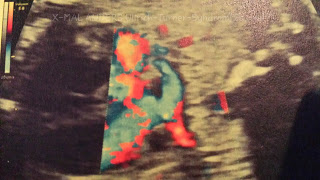

Das Herz eines Ungeborenen entwickelt sich zuerst. Es nimmt seine Arbeit bereits in der 5. SSW auf. Nährstoffverteilung steht dann auf dem Programm.

Probleme, Fehler oder Unstimmigkeiten im Konstrukt „Herz“ können fatal sein – nicht nur zu Beginn der menschlichen Entwicklung, wenn das mütterliche Herz für Zwei schlägt. Auffälligkeiten am Organ werden auch im Zusammenhang mit dem Ullrich-Turner-Syndrom untersucht. Vom Symptom „Herzfehler“ sind 23 bis 50 % betroffen.

Hoher Blutdruck und Herzgeräusche können auftreten. Eine Einengung/Verengung der Aorta oder eine Missbildung einer Herzkammer wären/sind verantwortlich dafür. Laut der Broschüre vom Bundesverband Herzkranke Kinder e.V. sind eben für UTS hauptsächlich bikuspide Aortenklappen (zwei-segelige Herzklappen) und Aortenisthmusstenosen (Einengung im Bereich des Bogens der Hauptschlagader) typisch.

Bei Krümelie stand pränatal Aortenklappenstenose auf dem Diagnosezettel. Da stand noch mehr, aber da ich keine Expertin bin und das alles nicht richtig ausführen und einschätzen kann, lasse ich es lieber. In ihren ersten zwei Lebensjahren entwickelte sich Krümelies Herz und heute ist sie sozusagen herzgesund. Ihre Auffälligkeiten haben sich relativiert.

Allgemein gilt, dass eine kardiologische Untersuchung – Kontrolle des Blutdrucks und Ultraschall – in regelmäßigen Abständen stattfinden sollte bei der Diagnose Ullrich-Turner-Syndrom.